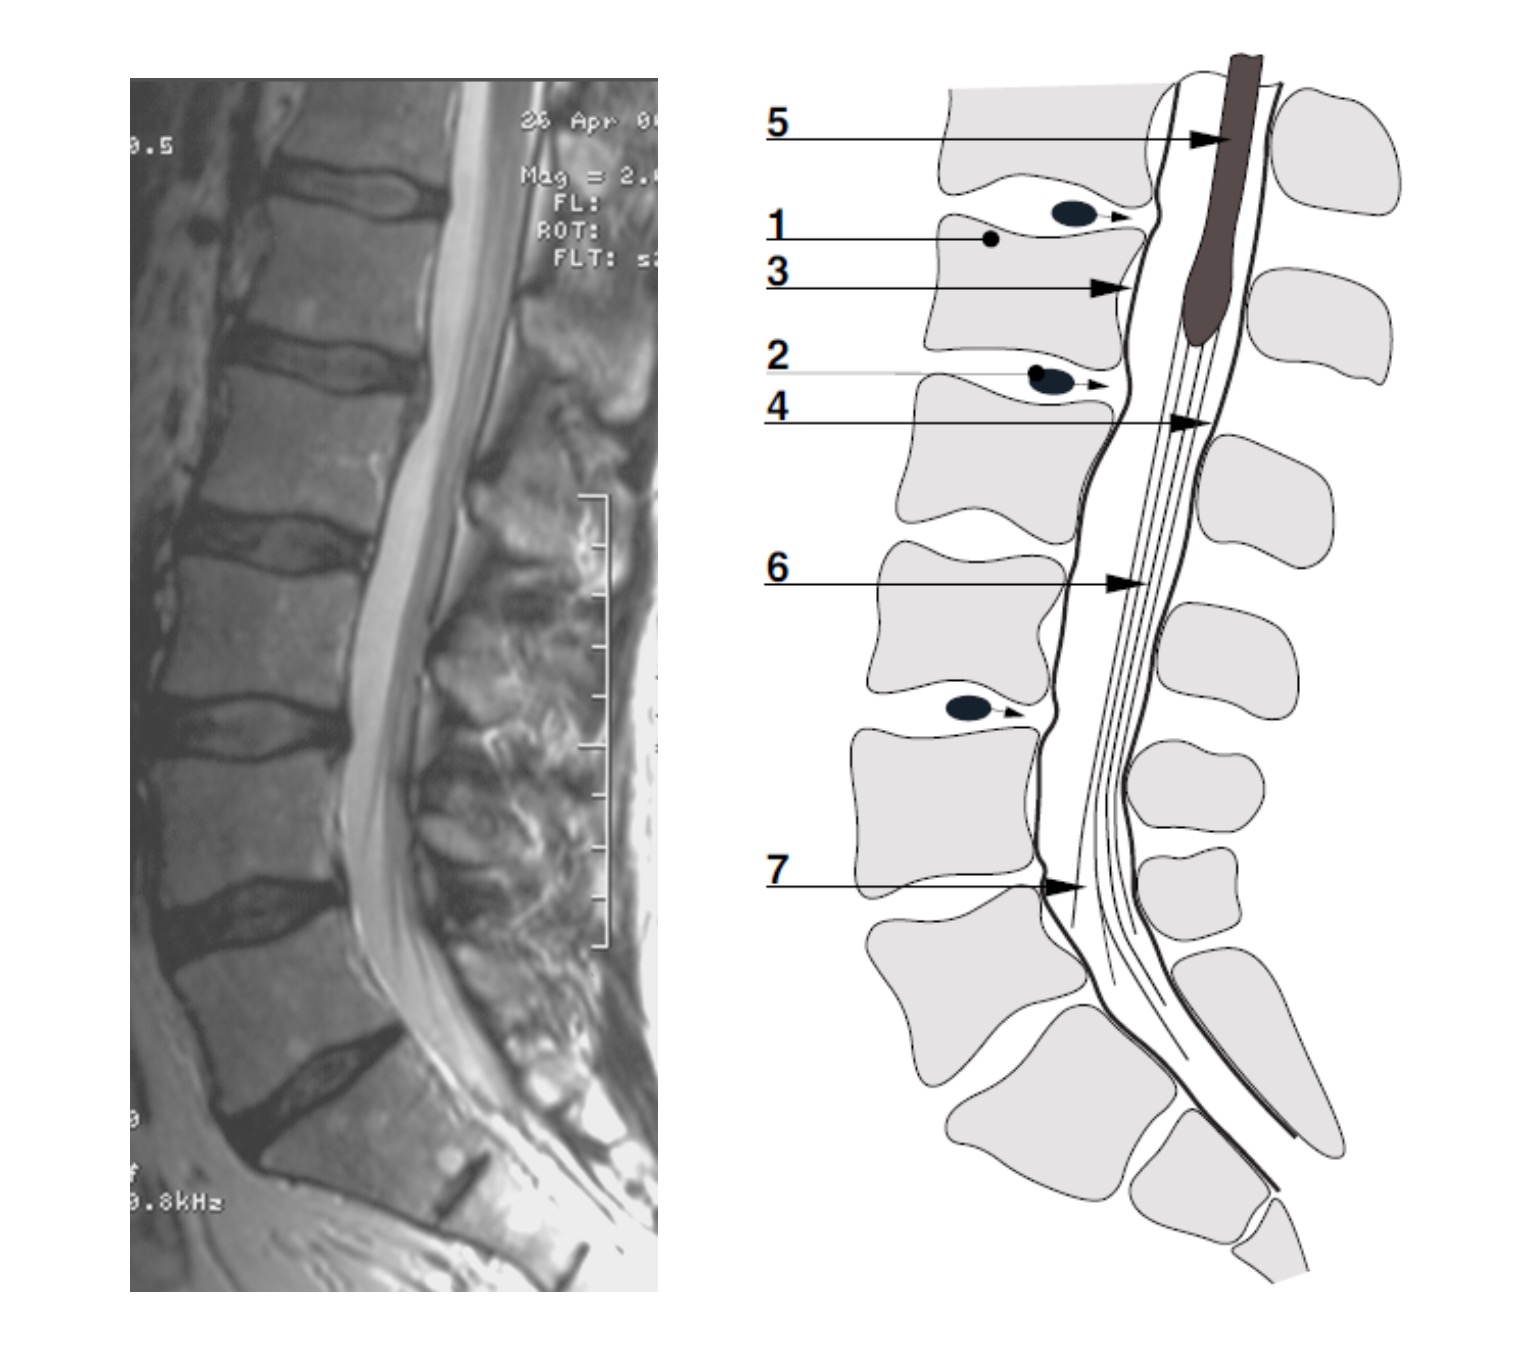

Figura nº 4. RMN columna lumbar (A. Ruiz de Azúa & J. Elizalde)

Plano sagital de una RMN de columna lumbo – sacra. Paciente de 44 años con una hernia vertebral L1-L2 y protusiones en L3-L4 y L4-L5.

1. L1.

2. Hernia en L1-L2 que protuye en el canal vertebral.

3. La duramadre separada de la parte posterior del cuerpo vertebral por la hernia L1-L2.

4. Duramadre en la zona dorsal del canal medular.

5. Medula espinal.

6. Conjunto “filum terminale” y “cauda equina”.

Elementos de la “cauda equina” en forma de abanico.